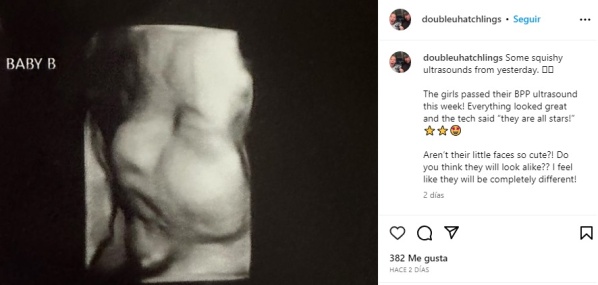

Hatcher espera entrar en trabajo de parto y dar a luz natural con medicamentos tanto a la beba A como a la beba B, o “las niñas”, como ella las llama cariñosamente, con una fecha de parto para Navidad. Se dice que ambos embriones están “prosperando”.